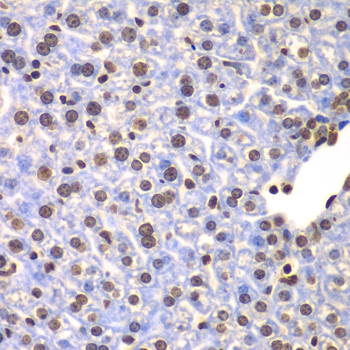

Immunohistochemistry of paraffin-embedded human oophoroma using ULK4 antibody at dilution of 1:100 (x400 lens).

Immunohistochemistry of paraffin-embedded human kidney cancer using ULK4 antibody at dilution of 1:100 (x400 lens).

Immunohistochemistry of paraffin-embedded human gastric using ULK4 antibody at dilution of 1:100 (x400 lens).

Immunohistochemistry of paraffin-embedded mouse liver using ULK4 antibody at dilution of 1:100 (x400 lens).